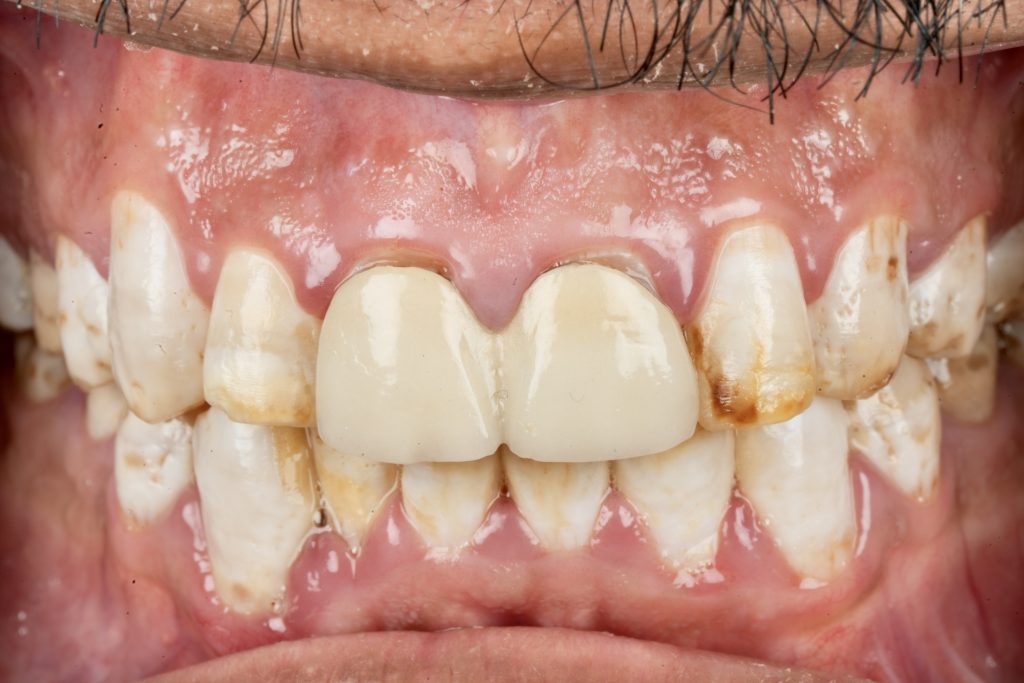

1️⃣ Diagnosis and Case Planning

The patient sought esthetic improvement for uneven incisal edges, discolored anterior teeth, and disproportionate gingival display (Fig 1). A digital smile simulation and mock-up try-in were performed to assess tooth proportion, midline alignment, and incisal curvature. The plan prioritized enamel conservation and optical harmony.